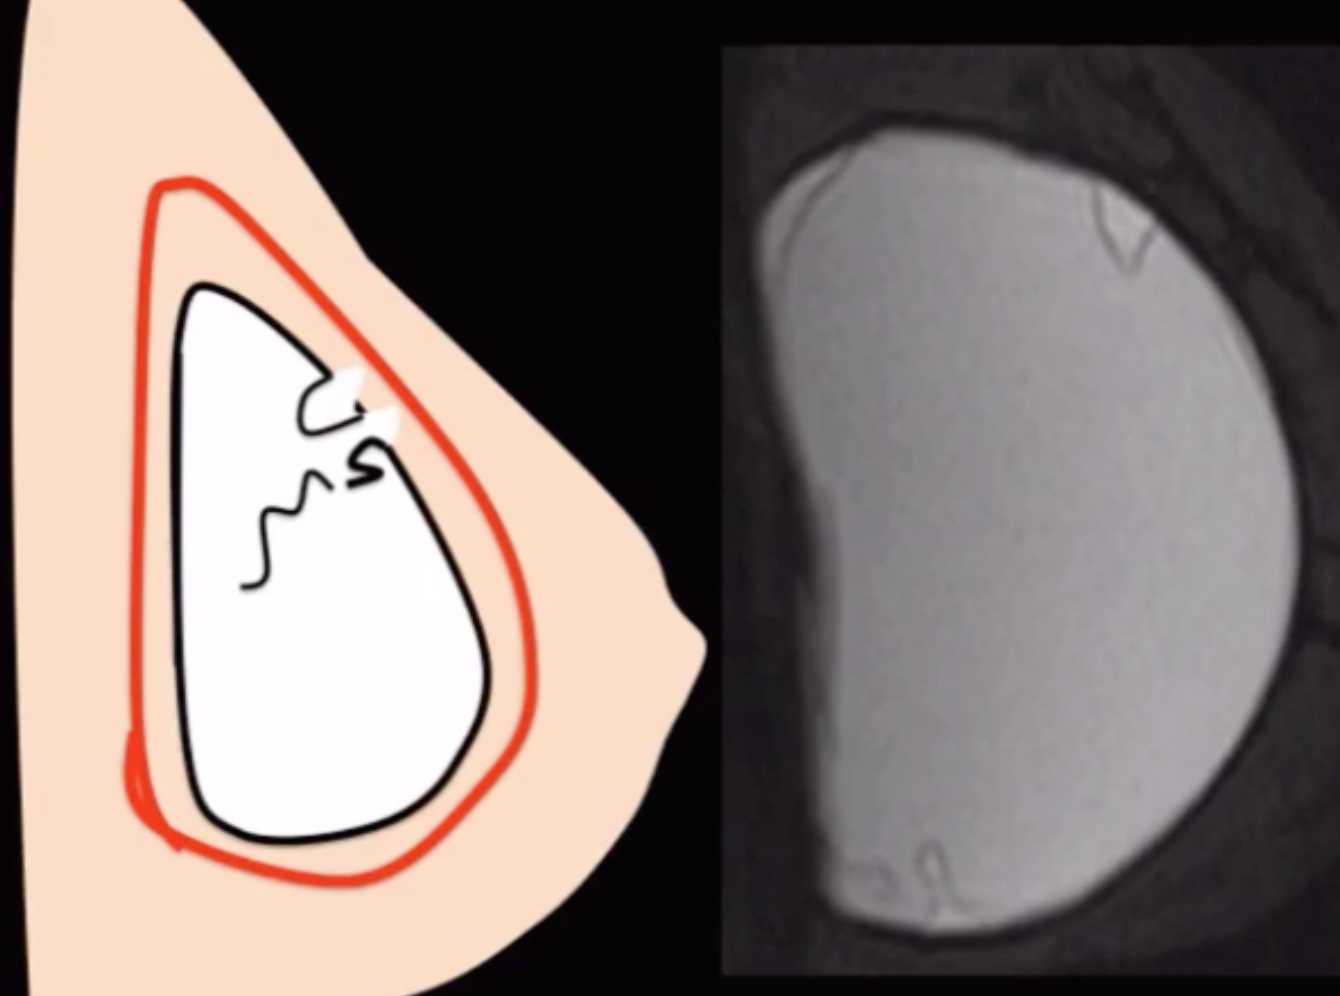

• Intracapsular rupture (80%) - Image 1

• Rupture of the container of the silicone implant but not the actual capsule (soft tissue capsule) itself

• Called linguine appearance

• Squiggle line will not have attachment to wall (radial fold will!)